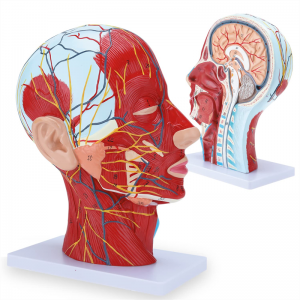

| Karatteristiċi | Il-mudell juri l-morfoloġija lokali tal-ġnub ta 'ġewwa u ta' barra tas-sezzjoni sagittali medjana tar-ras u tal-għonq, kif ukoll l-istrutturi tal-bastimenti tad-demm u n-nervituri, u hemm 84 partijiet li jindikaw sinjali b'kollox. |

【Mudell tal-muskolu newrovaskulari superfiċjali】 Dettaljat ħafna, numri mmarkati, li jistgħu jinqalgħu, japprofondixxu l-fehim tal-muskoli superfiċjali, bastimenti, nervituri u l-istrutturi interni tar-ras u l-għonq. Arterja ħamra, vetta blu, isfar-nerve.

【Karatteristiċi】 Juri l-muskoli superfiċjali tal-wiċċ espost; il-bastimenti tad-demm superfiċjali u n-nervituri tal-wiċċ u l-qorriegħa; l-istrutturi ta 'ġewwa tal-glandola parotida u l-passaġġ respiratorju ta' fuq; L-istruttura tas-sezzjoni trasversali sagittali tas-sinsla ċervikali.

Il-mudell wera l-morfoloġija lokali tas-sezzjonijiet sagittali medjali u laterali tar-ras u l-għonq u l-istrutturi vaskulari u tan-nervituri tiegħu, b'total ta '100 indikatur tas-sit.

Dan il-mudell huwa mudell ta 'muskolu newrovaskulari superfiċjali ta' ras u għonq naturali, komponent 1, li juri d-dettalji tar-ras tal-lemin u l-għonq u s-sezzjoni sagittali medjana, inklużi l-muskoli superfiċjali esposti tal-wiċċ, bastimenti superfiċjali tal-wiċċ u l-qorriegħa, in-nervituri u l-istruttura medjali tal-glandola parotida u l-passaġġ respiratorju ta 'fuq, u l-istruttura tas-sezzjoni sagittali tas-sinsla ċervikali